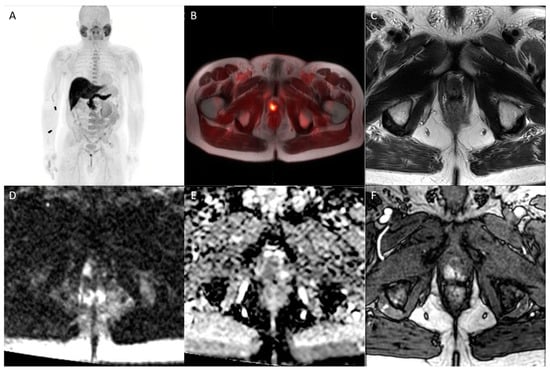

Figure 3. Whole-body maximum intensity projection (A), axial fused fluiclovine-PET/MRI (B), axial T2 (C), diffusion-weighted b2000 (D), apparent diffusion coefficient (E), and dynamic contrast-enhanced (F) images demonstrating focal uptake of radiotracer in the right prostatic apex peripheral zone with corresponding MR defined T2 hypointense lesion with associated restricted diffusion and focal asymmetric enhancement (PI-RADS 5), consistent with prostate cancer.

18F-fluciclovine functions as an analog of l-leucine amino acid, which is a transport protein preferentially upregulated in prostate cancer. Unlike many radiotracers used for prostate imaging, fluciclovine has minimal renal excretion, reducing confounding activity in the pelvis from urinary tract activity [59,60]. For initial staging, fluciclovine has limited value in localizing the primary prostate tumor, predominantly due to decreased specificity owing to overexpression in benign etiologies such as BPH and prostatitis [61]. However, fluciclovine performs better in the setting of biochemical recurrence, where updated NCCN guidelines recommend the consideration of fluciclovine PET imaging [62]. In the detection of extraprostatic disease, the tracer performs excellently, with a specificity of up to 100% for disease outside the prostate [63,64]. While the same studies demonstrated diminished specificity for detecting recurrent disease within the prostate itself, this highlights the role of concomitant mpMRI, as previously discussed (Figure 3).